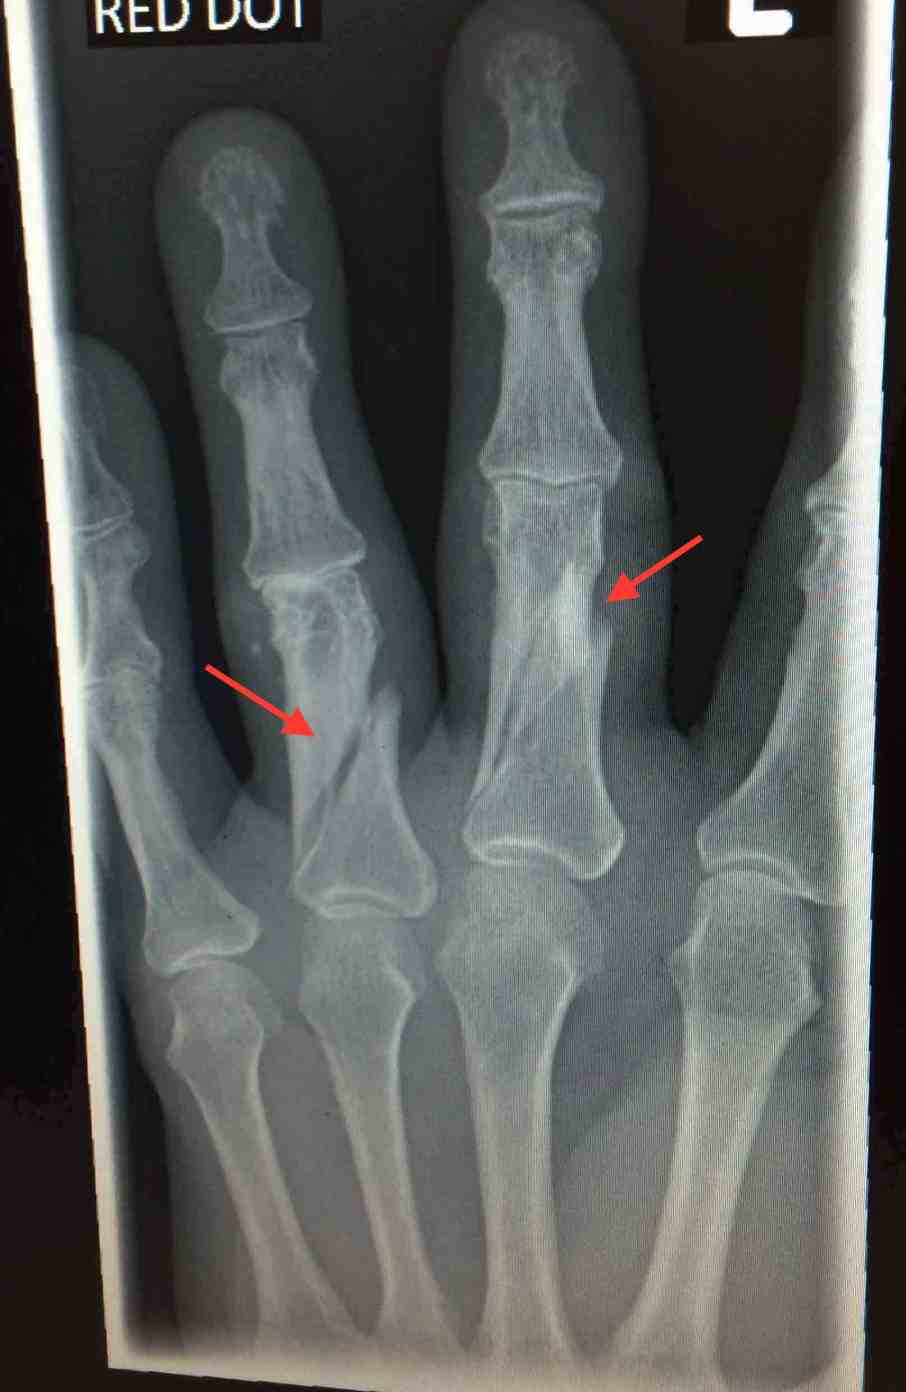

Spiral fractures; be careful in castles! Published August 12, 2016 at 1613 × 2479 in Northern Wales I: Conwy ← Previous Trackbacks are closed, but you can post a comment.